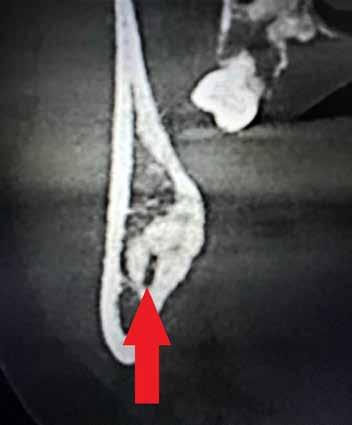

A CT metszetekben a 48-as gyökerei körbeölelik a canalis mandibularist, amelyet piros nyíllal jelöltünk a fotókon.

rációval tudom felszabadítani a koronát, másrészt, hogy a gyökerek 1-2 mm-nél ne kerüljenek közelebb a canalishoz. A fejlődési ütemüket követve, előreláthatólag kb. 15-16 éves korukra érik el a fogaik ezt az állapotot.

Szeretnék mutatni néhány ábrát az egyik bonyolult esetről, a közelmúltból. A CT-n látszik, hogy a három gyökér teljesen „körbenőtte” az ideget. Van olyan frontális metszeti kép, ahol csak a gyökerek vannak a nervus körül, ezen a szakaszon egyáltalán nincs meg a csontos fala a canalisnak. Szeparációs technikával, viszonylag könnyen, minimális traumával, szövődménymentesen sikerült eltávolítani a fog minden részét. A várakozásnak megfelelően, a beteg nem számolt be paraesthesiáról.